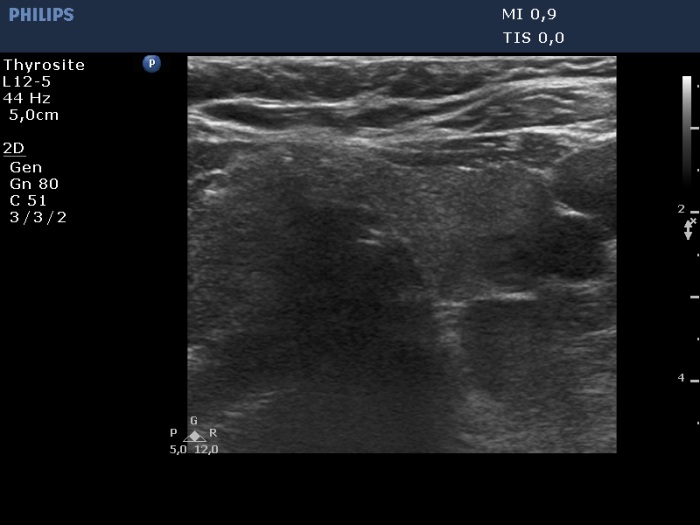

Ultrasonography. The thyroid was echonormal and had several insignificant hypoechoic lesions. There was a hypoechoic mass lower and dorsal to the lower pole of the left lobe.